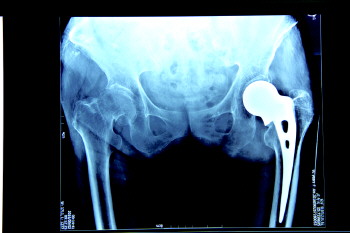

术后X光图